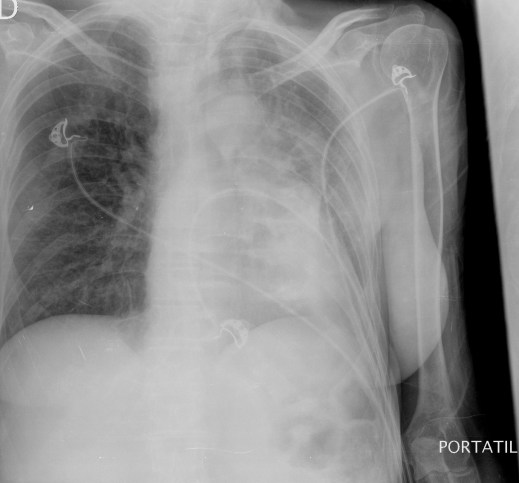

CASO: Operada de esofaguectomia y reconstrucción con coloplastia hace 3 meses. Sintomas de neumonía.

Hallazgos:

- De inicio llama la atención una densidad practicamente total del todo el hemitórax izquierdo, lo cual podría hacernos pensar que estamos ante una posible neumonía.

- Sin embargo el tórax está no está bien centrado, observar como la clavícula izquierda se encuentra casi en la mitad del pulmón, por tanto lo que vemos blanco es el mediastino ya que el tórax está rotado.

CENTRAJE:

El correcto centraje se determina comprobando que las extremidades internas de ambas clavículas equidistan de las apófisis espinosas vertebrales.

Mismo paciente, al cual esta vez se le ha tomado una radiografía en PA y en sedestación. Observar como las clavículas están equidistantes a las apófisis espinosas y como ha desaparecido el velamiento del pulmón izquierdo.

Por otra parte, paciente presenta una cardiomegalia y un discreto ensanchamiento del mediastino es probable relación con cambios postquirúrgicos.